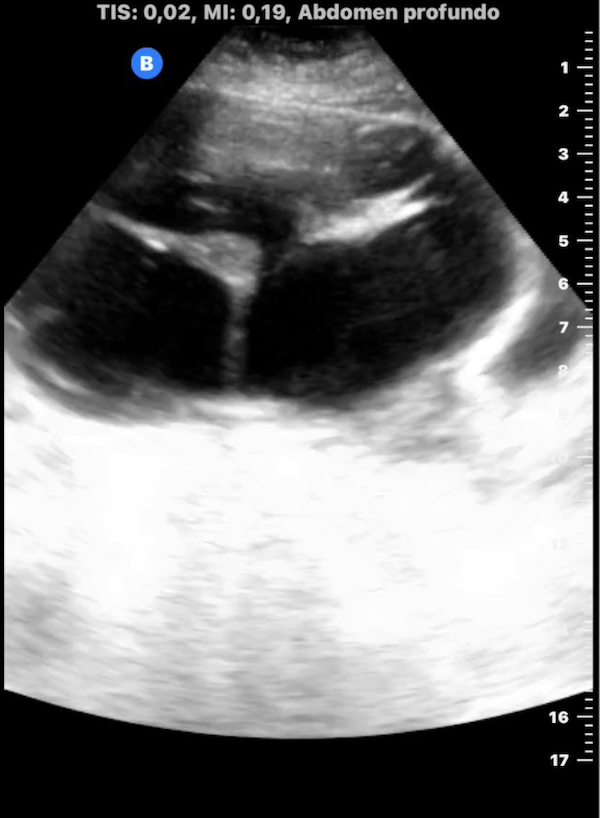

1. Mujer de 62 años; distensión abdominal; carcinoma de ovario.

2. Mujer de 46 años; dolor abdominal; masa ovárica a estudio.

3. Mujer 19 años; asintomática, ecografía durante curso de formación; hamartoma.

4. Mujer 32 años; dolor abdominal; quiste ovárico simple.

5. Mujer 27 años; ITU de repetición; ovario poliquístico.